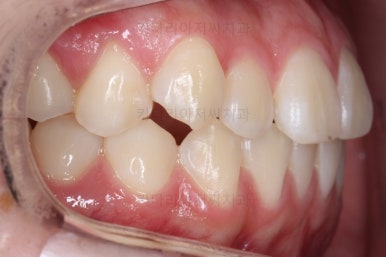

각설하고 위의 사진들은 부산치아교정잘하는곳 키다리아저씨치과에서 처음 내원하셨을 때의 사진입니다.

그리고 오른쪽 위 송곳니가 덧니처럼 볼록하여 웃거나 말할 때 자신감 있게 입을 벌리지 못하고 있었어요.

아랫니는 크게 심하지 않았고 윗니 앞니쪽에 치열이 삐뚤한 것을 볼 수 있어요.

그리고 위아랫니의 중앙선도 어긋나 있는 것으로 봐서 왼쪽과 오른쪽의 교합 자체도 다르고 문제가 있음을 알 수 있었어요.

각각 왼쪽, 오른쪽의 교합의 모습입니다.

가장 좋은 교합은 위아래 치아들이 지그재그로 톱니바퀴 물리듯이 맞아들어가야 하는데 오른쪽 사진들 보면 중간중간 빈틈도 많이 보여요.

이런 교합은 장기적으로 치아 수명을 단축시킬 수 있습니다.